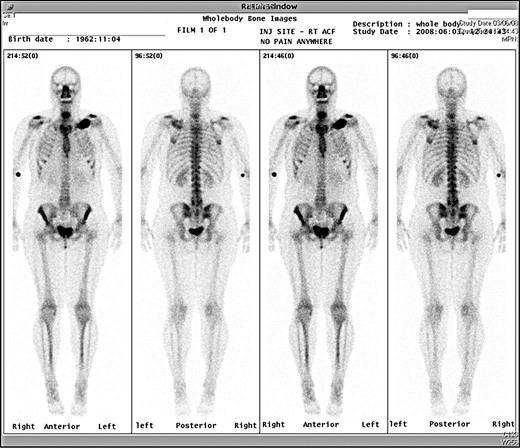

A 45-year-old woman presented with a 20-year history of a lump in the mid-third of the left clavicle, which had recently increased in size to 10 cm in diameter. Plain X-ray, computed tomography (CT) chest and clavicle, and bone scans were used to image the lesion (Figs 1–3). Radiology reported the lesion as a parosteal osteosarcoma, based on the CT appearance of tumour growing into the medulla of the mid-third of the clavicle; not usually a feature of an osteochondroma or an osteoma. Biopsies showed dense sclerotic bone, with no obvious malignant features. To confirm diagnosis complete excision of the tumour was needed, with a partial excision and scraping the lump off the surface deemed unsafe. The patient was informed that, following a total claviculectomy, a 30% functional loss (29.5% [8]) in her left shoulder power would be expected. Her active lifestyle meant this result was unacceptable, so she opted instead for excision of the tumour plus the adjacent clavicle, irradiation and reimplantation of the bone with internal fixation, despite this being relatively experimental. If successful, she would have virtually normal function. Although possible risks included infection or development of non-union, which would require further surgery or possible complete claviculectomy, it was deemed oncologically safe with a low risk of complications.